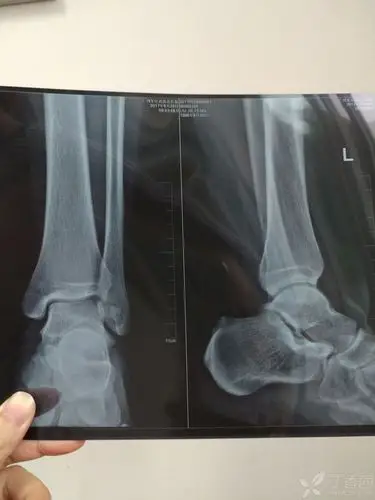

多见于老年患者,当有脚后跟痛时,经过拍摄x光片,可以发现跟骨结节处有

踝关节,正位和侧位x线照片

请骨科战友帮忙看一下左踝关节x线片 [病例帖]